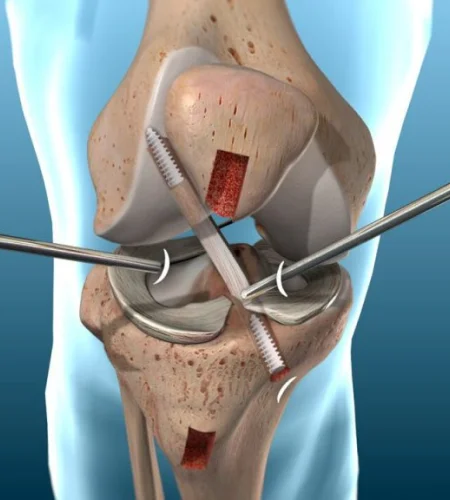

PCL Reconstruction

Surgical repair of the posterior cruciate ligament to restore knee stability.